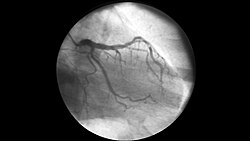

Коронарографи́я (лат. coronography — «рисование сосудов сердца»[1], или лат. coronarius — «относящийся к венку, напоминающий венок»[2] и лат. -graphia — «запись»)[3] — рентгеноконтрастное исследование, которое считается «золотым стандартом» диагностики ишемической болезни сердца (ИБС). Оно позволяет с максимальной точностью увидеть состояние коронарных артерий: где именно, насколько сильно и в каком виде они сужены или закупорены. Процедура даёт врачу-кардиологу полную картину и помогает сразу принять решение о тактике лечения.

Исследование инвазивное: в условиях операционной через артерию (обычно на руке или бедре) вводят тонкий катетер, по которому подают контрастное вещество непосредственно в сосуды сердца, одновременно выполняя рентгеновскую съёмку. В момент прохождения контраста по сосуду делают рентген-снимки (ангиограммы), на которых видно, как заполнен просвет артерии, есть ли сужения (стенозы), окклюзии, а также особенности кровотока[4].

Процедура проводится в специальной рентген-операционной на аппарате ангиографе. Это современная установка, которая позволяет видеть сосуды в реальном времени на большом экране. Под местной анестезией делают небольшой прокол в лучевой артерии (на запястье) или бедренной (в паху). Через этот прокол вводят тонкий гибкий катетер. Под контролем рентгена катетер аккуратно проводят по артериям до устьев коронарных сосудов сердца (путь обычно от руки или бедра до самого сердца). Через катетер порционно вводят рентгеноконтрастное вещество. Как только контраст заполняет коронарные артерии — они становятся отчётливо видны на экране ангиографа. Делается серия снимков и видеозапись. Врач сразу видит точное расположение, степень и характер сужений (стенозов) или закупорок. Если обнаруживается значимое сужение — прямо во время той же процедуры можно выполнить стентирование. По тому же катетеру или новому подводят специальный баллон со стентом (металлическая сеточка). Баллон раздувают — стент раскрывается и расправляет сосуд, восстанавливая нормальный кровоток. Разрезов и вскрытия грудной клетки для проведения коронарографии не требуется[4][5].